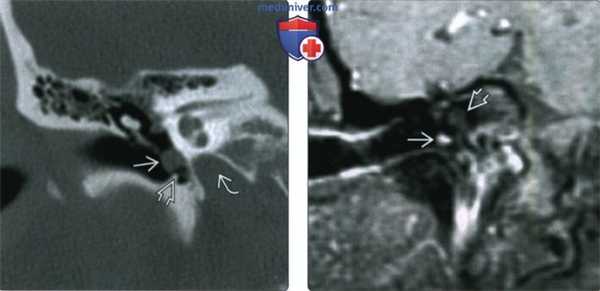

(Слева) КТ без КУ, изоденсная опухоль, расположенная в правом сонном пространстве. Шиловидный отросток смещен в латеральную сторону. И хотя шиловидный отросток чаще располагается кпереди от сонного пространства, вагальные параганглиомы обычно смещают его в латеральную сторону, а не вперед.

(Справа) МРТ Т2ВИ STIR, этот же пациент. Сигнал от опухоли умеренно гиперинтенсивный. Внутренняя сонная артерия смещена вперед и в медиальную сторону, шиловидный отросток смещен в латеральном направлении.

(Слева) МРТ Т1ВИ FS с КУ, достаточно небольшая опухоль блуждающего гломуса слева. Сравните положение внутренней сонной артерии, яремной вены и шиловидного отростка со здоровой и с пораженной сторон.

(Справа) МРТ Т1ВИ, сагиттальная проекция. Новообразование с четкими контурами и сигналом промежуточной интенсивности. Обратите внимание, что образование имеет извитую форму и расположено вдоль длинной оси сонного пространства. На сагиттальном срезе видно, что окологлоточная жировая клетчатка смещена вперед.